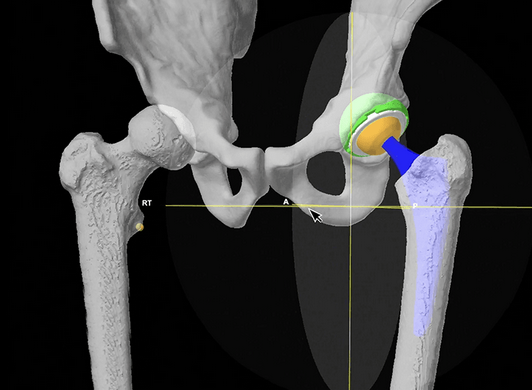

5. Computer navigation

stryker CT navigation

Stryker Mako Robot Navigation

Clave et al Orthop Traumatol Surg Res 2015

- 325 cases THA with computer assistance

- 83% of leg length restored to within 5 mm of contralateral hip

- 88% of offset restored to within 5 mm of contralateral hip